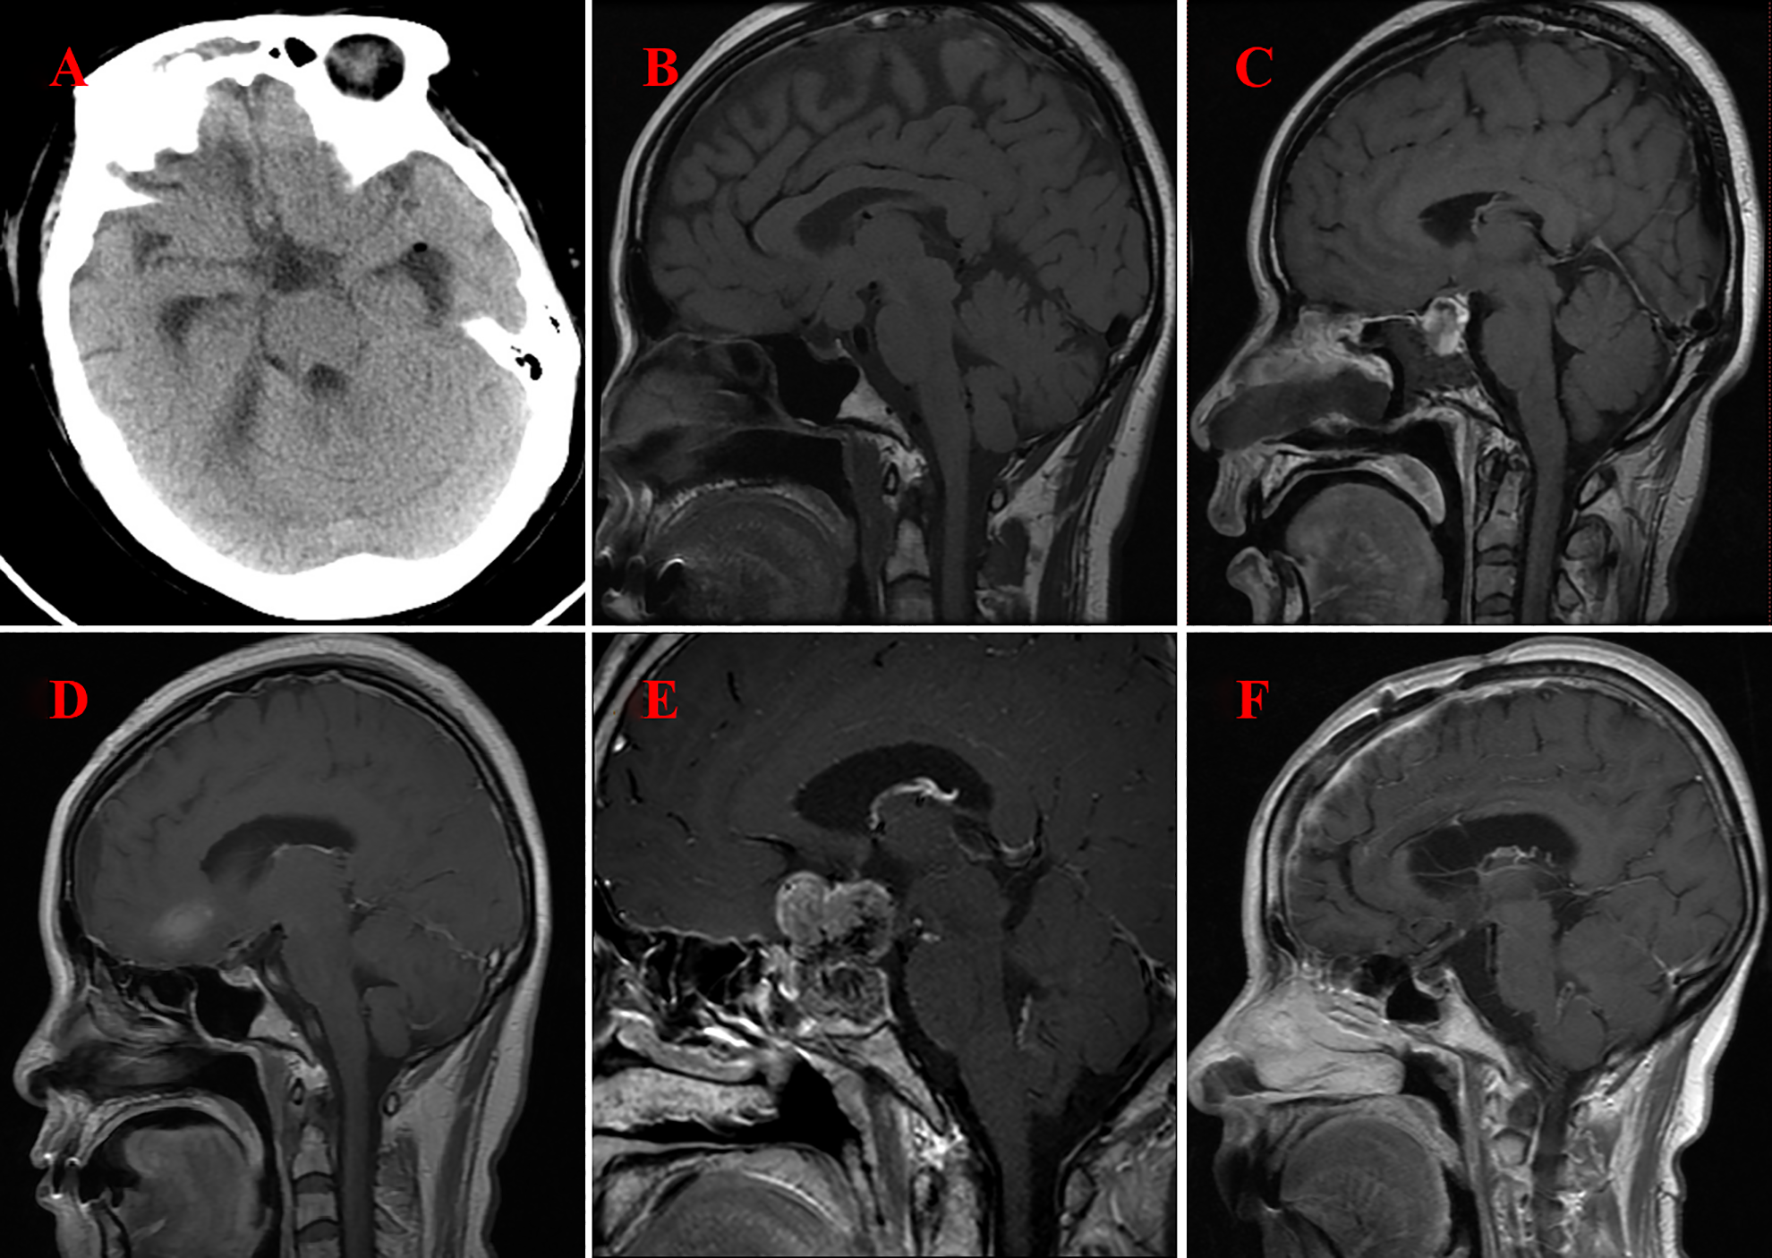

The follow-up duration for all patients spanned from 1.5 to 6.0 years, with each individual successfully completing the period. Figure 3 shows the follow-up imaging results of six patients. The follow-up assessments revealed that all six patients demonstrated varying degrees of improvement in preoperative symptoms, such as headaches and visual field disorders. One patient, who underwent subtotal resection, experienced a recurrence two years postoperatively and subsequently underwent a second total resection, with no recurrence observed during the ensuing 1.5-year follow-up. The remaining four patients who underwent total resection exhibited no signs of recurrence or metastasis throughout the follow-up period. Postoperatively, one patient developed transient diabetes insipidus, which resolved gradually during the follow-up period. In contrast, two patients developed persistent diabetes insipidus, and three patients exhibited hypopituitarism. These conditions were managed with the long-term administration of desmopressin acetate tablets and hormone replacement therapy.

Figure 3

Imaging following surgery for GCT of the neurohypophysis. (A) CT scan of the brain indicates complete resection of the tumor located in the suprasellar region (Case No. 1). (B) MRI of the brain with contrast illustrates complete resection of the tumor within the prepontine cistern, suprasellar area, and the floor of the third ventricle (Case No. 2). (C) MRI of the brain with contrast reveals postoperative changes in the sellar region, characterized by minimal fluid accumulation (Case No. 3). (D) MRI of the brain with contrast again demonstrates complete resection of the tumor in the suprasellar region (Case No. 4). (E) MRI of the brain with contrast indicates the presence of residual and recurrent tumor in both the intrasellar and suprasellar regions(Case No. 5) (F) MRI of the brain with contrast confirms complete resection of the tumor in the intrasellar and suprasellar regions (Case No. 6).